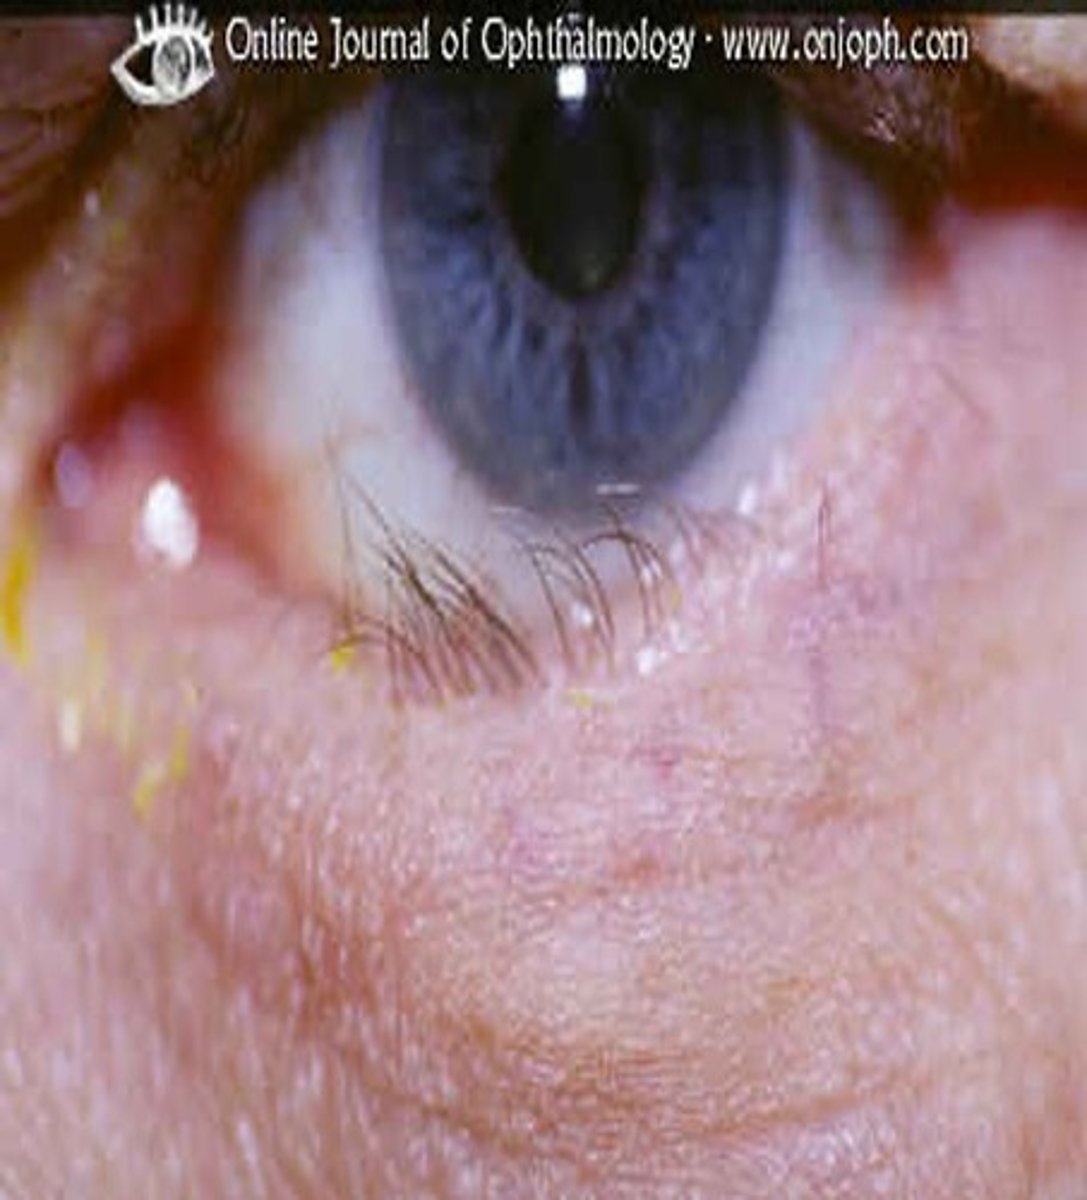

what is a pinguecula?

benign connective tissue overgrowth that appears yellow and doesn't normally affect vision

what is ectropion?

out-turning of the lid margin

- more common in older patients

-occurs with less functional CN III- parasympathetic fibers that control the lower eyelid (orbicularis oculii)

what is entropion?

inward turning of the lid margin

- normally due to scaring or inflammation

- can cause damage and affect vision due to inward lashes